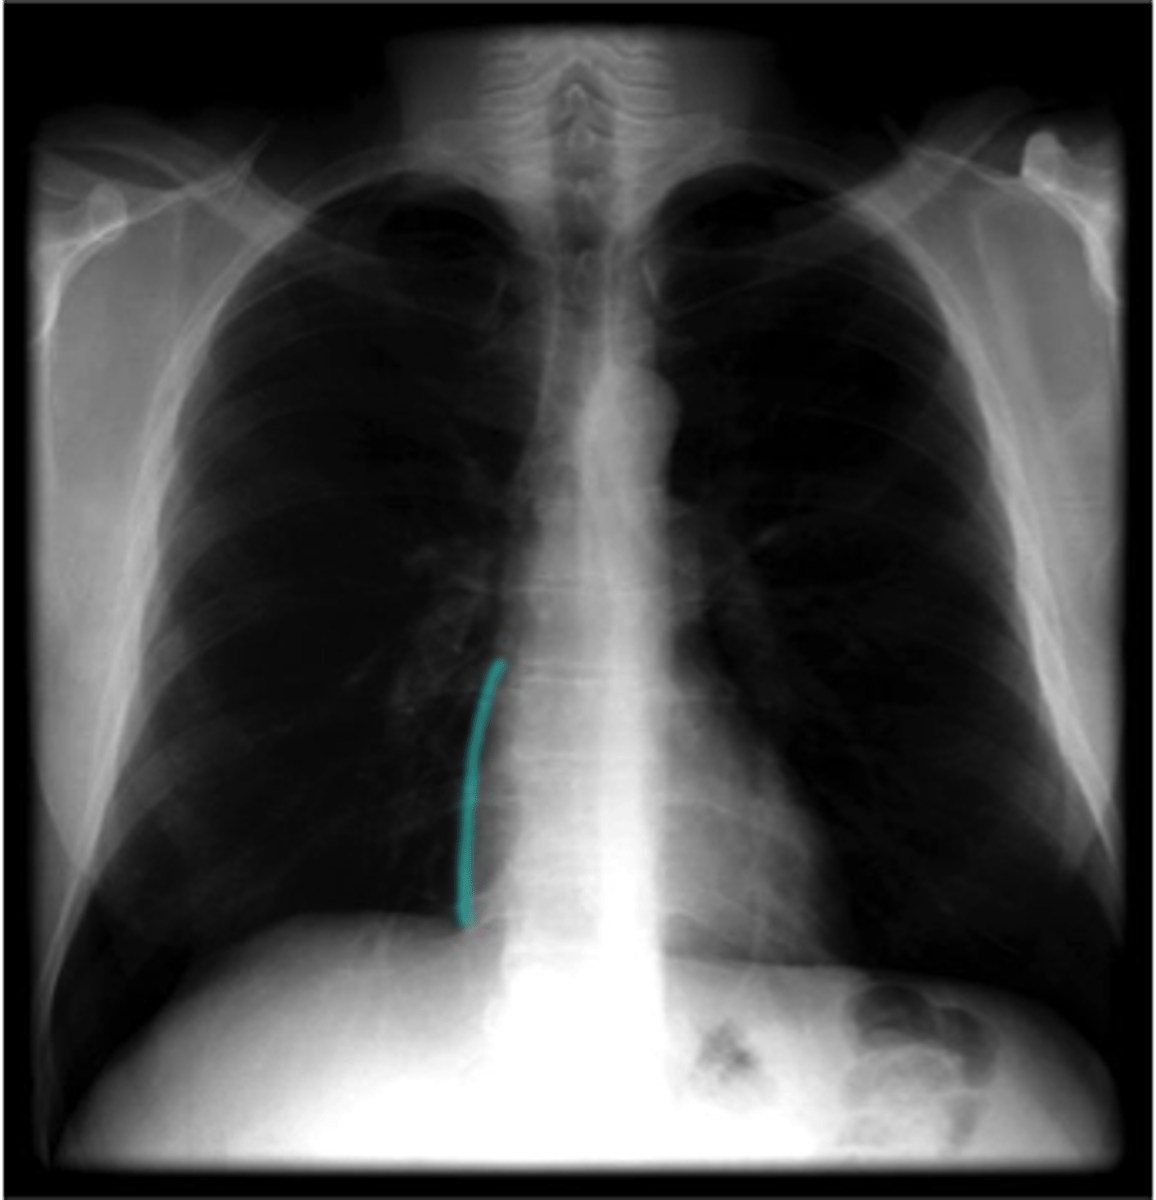

anterior interventricular sulcus